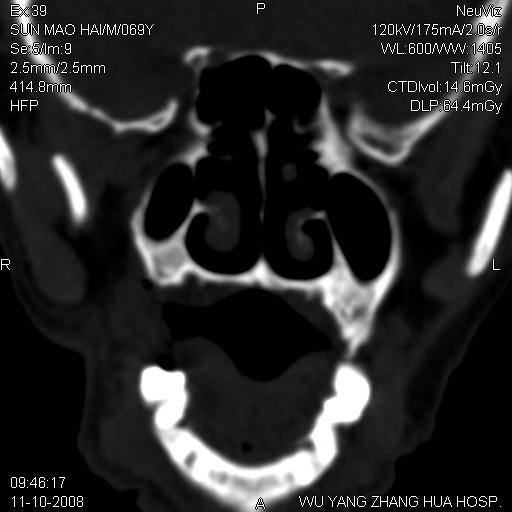

标题: CT16568:右面部瘘管半年余,无其它不适.

考虑右上颌异位齿(或斜向阻生齿)并根尖脓肿。

1.右上颌异位齿

2.右上颌化脓性骨髓炎

3.右下鼻甲肥大